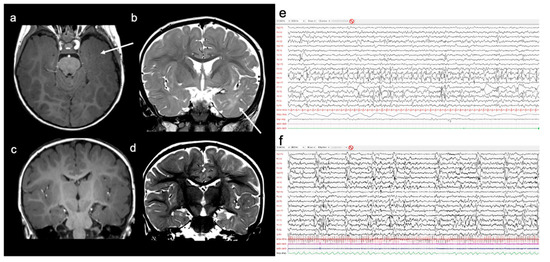

2. Case Report